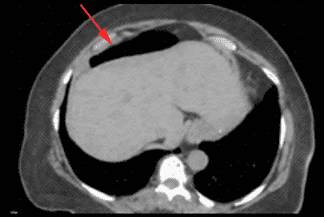

Descrição das imagens: Tomografia computadorizada do abdome evidenciando a interposição colônica no hipocôndrio direito.

Sinal de Chilaiditi: Descrição rara do posicionamento do intestino entre o fígado e o diafragma.

• Tomografia computadorizada do abdome: E m geral, solicitada quando há algum tipo de dúvida na interpretação da radiografia. A tomografia ajuda a definir com clareza a interposição da alça colônica entre o fígado e diafragma direito.